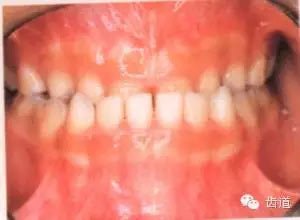

3.上下牙弓的高度關(guān)系:前牙有否深覆合或開(kāi)合。

前牙覆合:上前牙切端蓋過(guò)下前牙牙冠的長(zhǎng)度。

前牙深覆合:上前牙冠覆蓋下前牙冠超過(guò)1/3。分為3度。

前牙開(kāi)合:上下前牙切端間無(wú)覆合關(guān)系,垂直向呈現(xiàn)間隙。亦可分為3度。

87.jpg

前 牙 覆 合

正常覆合:上前牙牙冠覆蓋下前牙牙冠切端在1/3以內(nèi)。

深覆合

開(kāi)合

I度

上前牙牙冠覆蓋下前牙超過(guò)冠1/3而不足1/2者

上下前牙切端垂直向間隙在3mm以內(nèi)

II度

超過(guò)冠1/2而不足2/3者

在3—5mm之間

III度

超過(guò)冠2/3者

在5mm以上